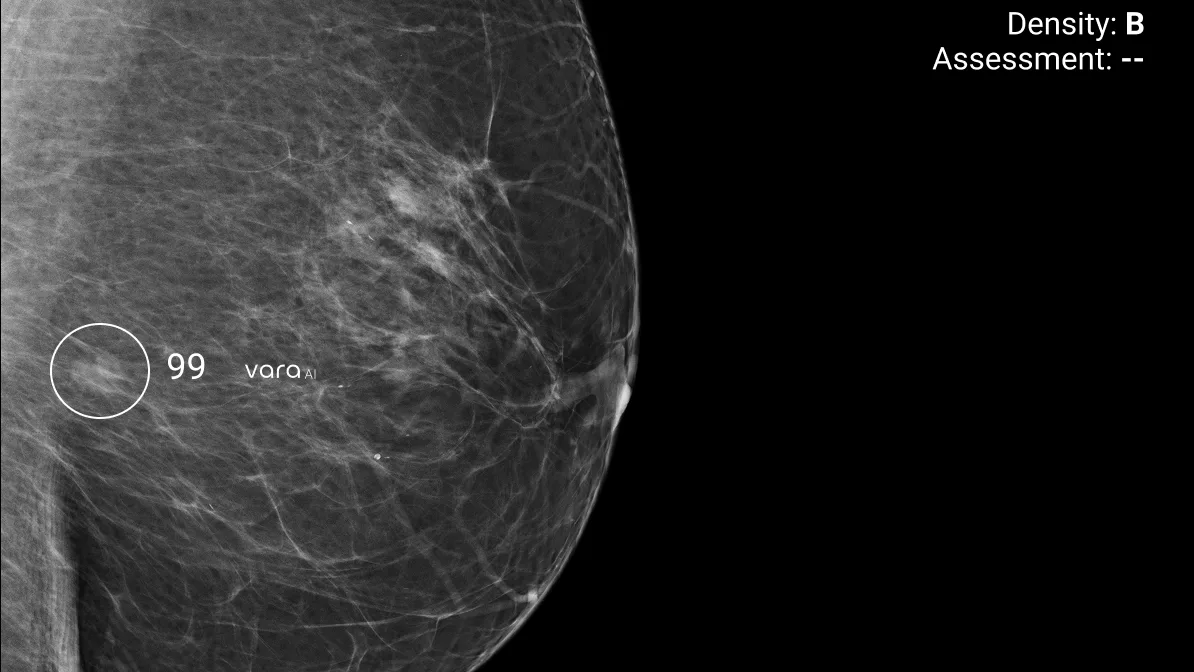

La IA que mejora en un 16,7% la detección del cáncer de mama

Un estudio reciente publicado en Nature Medicine, elaborado con la participación de 460.000 mujeres, ha demostrado que el sistema de mamografía con IA de Vara aumenta las tasas de detección de cáncer en un 16,7%, reduce en un 15% las pruebas de seguimiento innecesarias debidas a falsos positivos y disminuye en un 60% la carga de trabajo de los radiólogos.

Vara cuenta además con la certificación de la CE como “segundo lector independiente”, lo que significa que podría sustituir al segundo radiólogo en los programas de doble lectura manteniendo los estándares de calidad exigidos por la normativa europea.